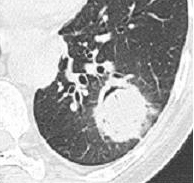

La fièvre persiste malgré les antibiotiques. Cela fait maintenant 5 jours, et vous décidez donc de réaliser un scanner thoracique dont les images sont les suivantes.

Question 13 : Comment décrivez-vous ces images ?

Nodule pulmonaire entouré de verre dépoli

Présence d’un épanchement pleural gauche

°précoce : signe du halo : nodule unique ou multiple, avec verre dépoli autour (signe du grelot se voit dans l’aspergillome compliquant une caverne tuberculeuse par exemple) ;

°plus tardif : condensation non spécifique, puis apparition d’un croissant gazeux traduisant la nécrose du parenchyme.